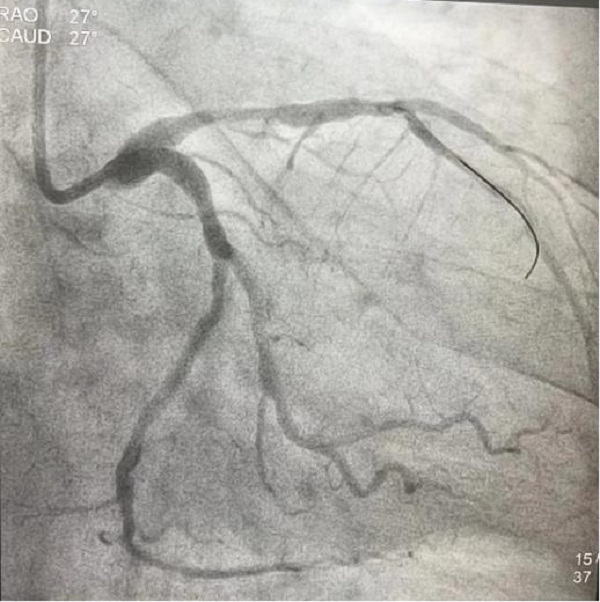

时间紧迫,容不得丝毫犹豫,刘积伦主任团队在告知患者家属相关病情后,立即为患者进行了紧急冠脉造影及支架植入术。手术中,医护人员每一个动作都精准而果断,很快,闭塞的血管被成功开通,恢复3级血流,王先生的心脏重新焕发了生机。